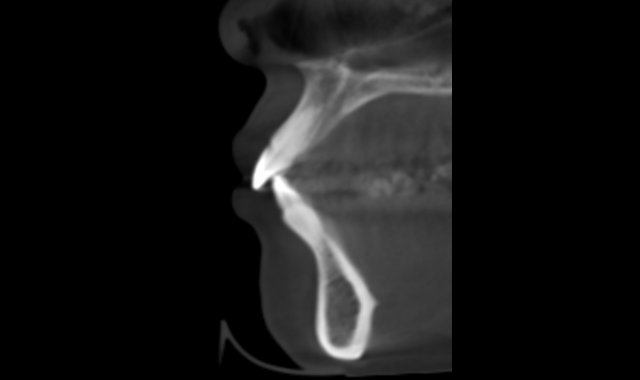

The initial scan was taken with a 400 μm voxel size at 90 kV, a 10 mA setting. The scanning time was 13.887 seconds. The machine used was a Planmeca ProMax 3D Mid. The radiograph in Figure 1 has a thickness of 5.2 mm. Though the alveolar housings are thin, the teeth seem to be well encapsulated in bone. Figure 2 is the 3D construction of this same area. A LFOV progress scan (dental only) was taken to evaluate the root alignments. The scan was taken at a 200 μm voxel size, 90 kV, 5 mA, in 4.044 seconds.

Fig. 1